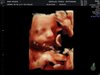

U mnie wszystko pięknie tylko te kości i udowe są o 3 dni mniejsze . A to moje piękności [emoji307] [emoji307] [emoji307]

IMG_20180626_1_13.jpg

• IMG_20180626_1_13.jpg

40,5 KB · Wyświetleń: 431